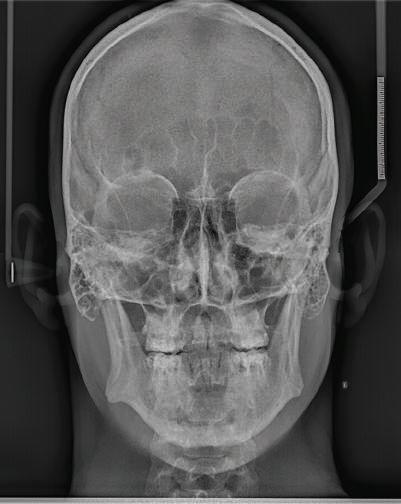

Пациентът постъпи в моята клини ка с наличие на темпоромандибуларен дисфункционален болков синдром, едно странно изместен диск с редукция в дяс ната става, клас II, подклас 2, тесни гор на и долна челюст със струпване, дъл бок овърбайт

орални снимки и снимки на позата, пал пация на мускулите, брукс-чекър, оклу зограми, кондилография, рентгеногра фии, СВСТ и ядрено-магнитен резонанс на темпоромандибуларните стави). Преди началото на ортодонтското лечение всички стари възстановява ния бяха свалени и бяха заменени с дъл госрочни временни от хибридна керами ка. На девитализираните зъби бе прове дено ендодонтско релечение. Индивиду ализиран оклузален сплинт бе направен с цел да се постигне контролирано репо зициониране на долната челюст, като носенето му продължи три месеца до възстановяване на правилната позиция на ставния диск и затихване на орофаци алната болка и дискомфорт в ставата. Брекетите в горната челюст бяха за лепени, за да започне подреждането и нивелирането на зъбите, докато паци ентът все още носеше сплинта. След края на терапията със сплинта бе на правена кондилография, за да се потвър ди триизмерната позиция на долната челюст. След залепване на брекетите в долна

и гингивална усмивка. Започнахме лечението с пълна диагно стика (анамнеза, интраорални, екстра